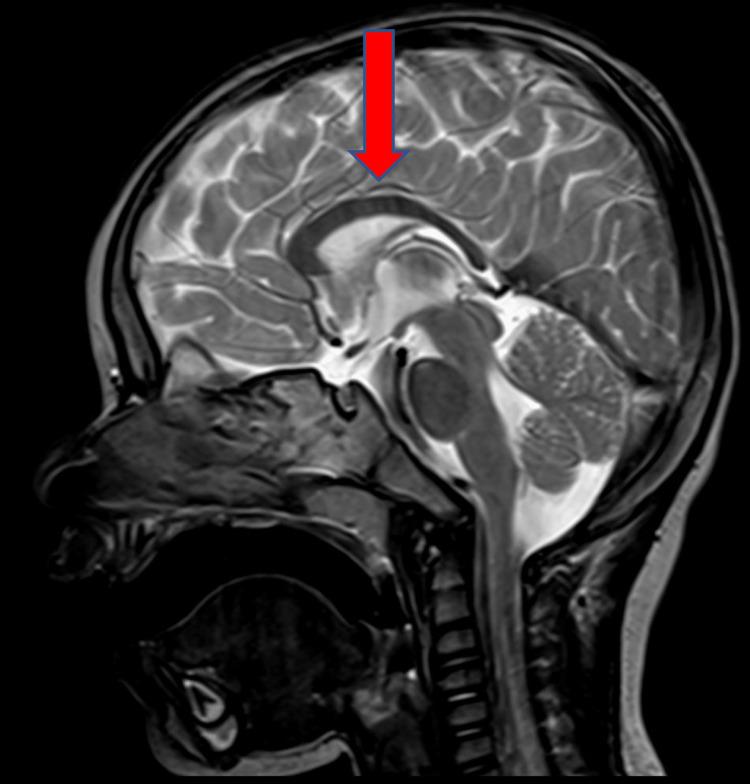

Pitt-Hopkins syndrome (PTHS) is a rare, neurodevelopmental genetic disorder caused by mutations in the TCF4 gene. This gene encodes a ubiquitous, class I, basic helix-loop-helix factor, which is implicated in various developmental and regulatory processes. Predominant clinical manifestations of PTHS include facial dysmorphisms, intellectual disability, absence of expressive language, epilepsy, as well as visual and musculoskeletal impairments. Gastrointestinal (GI) complications, such as chronic intestinal pseudo-obstruction, gastroparesis with delayed bowel transit, chronic constipation culminating in failure to thrive, and gastroesophageal reflux disease (GERD), are also prevalent in these patients. The early identification of pain etiology in PTHS patients poses a significant clinical challenge. This report presents two cases of PTHS patients suffering from gastrointestinal dysmotility, evaluated at our Pediatrics Clinic at the "Microcitemico" Hospital. A review of existing literature was conducted via the PubMed database to elucidate the current understanding of the GI phenotype in PTHS. Twenty articles were deemed most relevant and selected for this purpose. In both patients, severe constipation and abdominal distension resulted in persistent agitation and inconsolable crying. These distress symptoms were completely ameliorated following prompt pharmacological intervention.

皮特-霍普金斯综合征(PTHS)是一种罕见的神经发育性遗传疾病,由TCF4基因突变引起。该基因编码一种普遍存在的I类碱性螺旋-环-螺旋因子,参与各种发育和调节过程。PTHS的主要临床表现包括面部畸形、智力残疾、无表达性语言、癫痫以及视觉和肌肉骨骼损伤。胃肠道(GI)并发症,如慢性肠道假性梗阻、胃轻瘫伴肠道运输延迟、慢性便秘最终导致发育不良以及胃食管反流病(GERD),在这些患者中也很常见。早期识别PTHS患者的疼痛病因是一项重大的临床挑战。本报告介绍了两例在“Microcitemico”医院儿科诊所接受评估的患有胃肠道动力障碍的PTHS患者。通过PubMed数据库对现有文献进行了综述,以阐明目前对PTHS胃肠道表型的理解。为此选择了20篇最相关的文章。在这两名患者中,严重便秘和腹胀导致持续烦躁和无法安抚的哭闹。经过及时的药物干预,这些痛苦症状完全得到缓解。